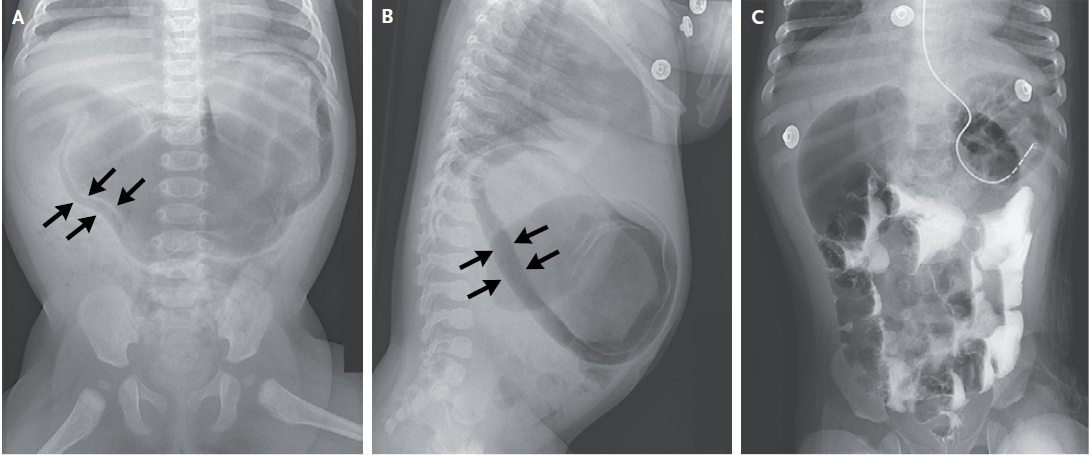

Для оказания медицинской помощи поступила 4-х месячная девочка с нарушением питания и не содержащей желчи рвоту. В возрасте 1 месяц она уже была госпитализирована с такими же симптомами, но в последующем ее питание относительном наладилось. При поступлении живот вздут, в то же время мягкий. При лабораторном исследовании выявлен гипохлоремический метаболический алкалоз, при рентгенологическом исследовании – пневматоз желудка (рис. А и В). Был установлен назогастральный зонд, начата внутривенная инфузионная терапия. При рентгенологическом исследовании верхних отделов желудочно-кишечного тракта с контрастом зафиксировано поступление его в тонкий кишечник; последующие снимки зафиксировали разрешение пневматоза и «двойной пузырь газа», что предполагал непроходимость на уровне двенадцатиперстной кишки (рис. С). Интраоперационно диагностирована перетяжка двенадцатиперстной кишки. Выполнен дуоденодуоденостомия, что привело к разрешению симптоматики. Пневматоз желудка является редким осложнением, вероятно, развивается вследствие повреждения слизистой вследствие ишемии или инфекции, что допускает возможность газа инфильтрировать стенки желудка. У новорожденных пневматоз обычно является следствием некротического энтероколита.